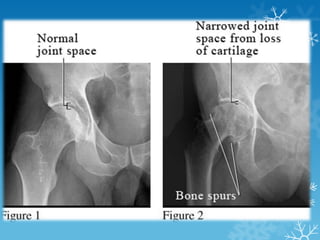

 X-rays: Loss of joint cartilage, narrowing

bones, and bone spur formation.